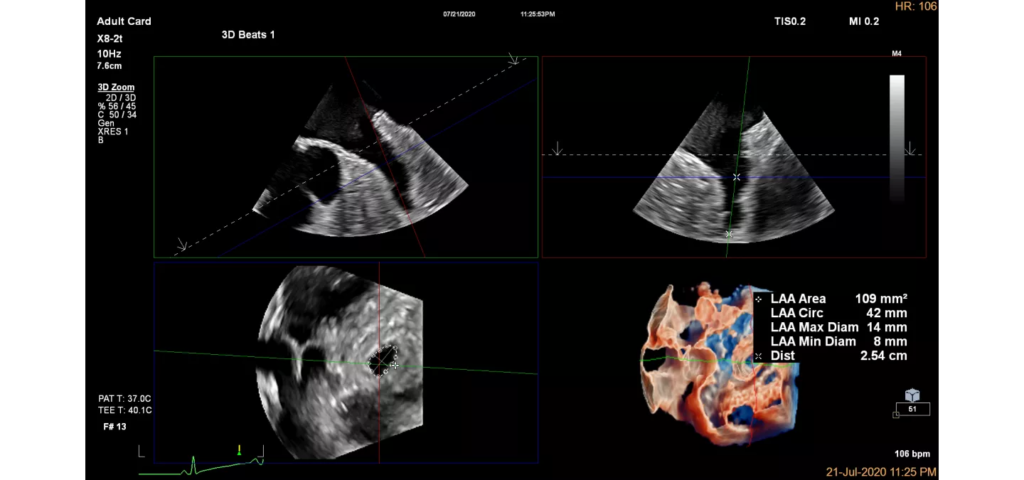

EPIQ CVx, our premium cardiovascular ultrasound system built on our innovative, modular, industry-leading ultrasound platform, has powerful AI-based capabilities and advanced diagnostic solutions to help you transcend today’s complexities and propel echocardiography into the next dimension. This enables you to achieve greater consistency, accessible innovation, smarter workflows, and easier scalability.

Epiq CVx